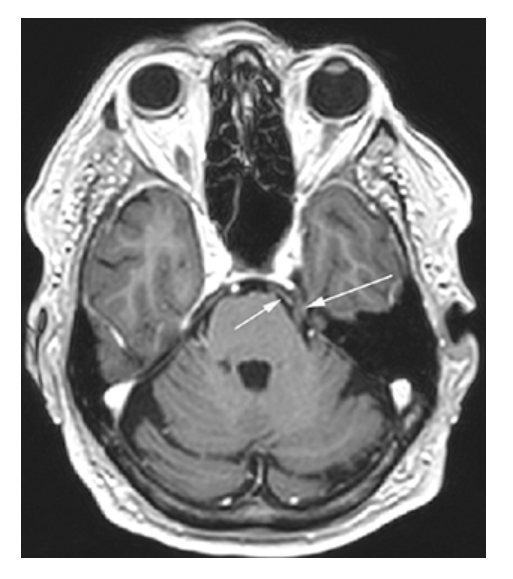

Neurovascular Compression Syndrome. MRA-TOF shows contact between the left posterior cerebral artery (PCA) (short arrow) and the left trigeminal nerve CN 5 (long arrow). In this individual, the vascular loop induced trigeminal neuralgia.